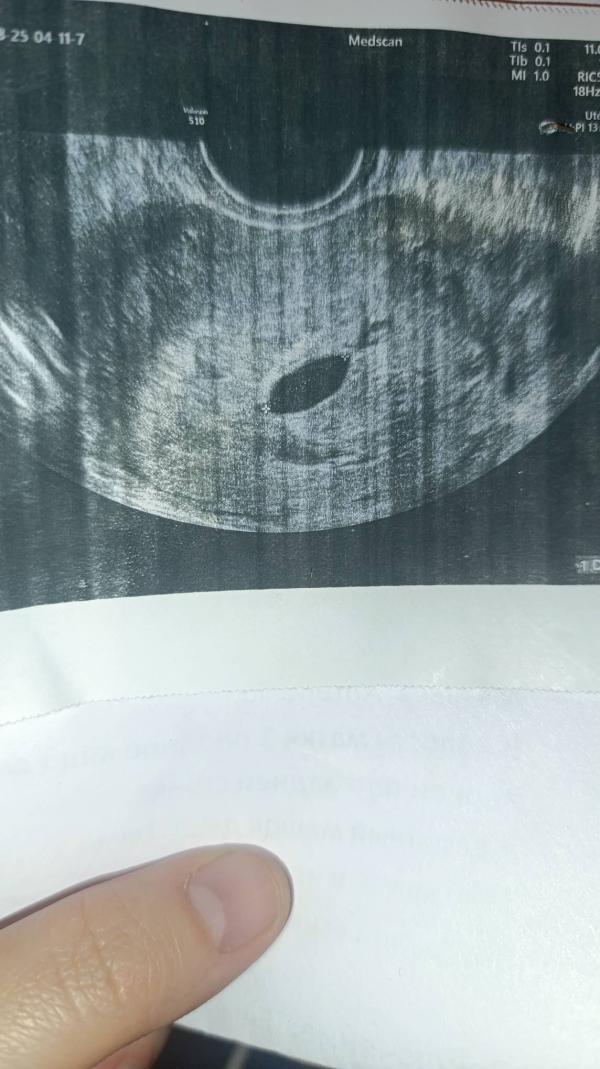

Сегодня на УЗИ потвердилась замершая беременность. На душе пустота , на глазах слезы . Разумом я понимаю , что на все врля Аллаха. Но сердце и душа болит 🥺💔